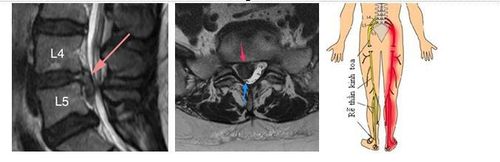

Hình bên trái là mặt cắt dọc các đĩa đệm bình thường (trong các vòng tròn đỏ). Hình bên phải là mặt cắt ngang đĩa đệm bình thường (trong vòng tròn đỏ), ống sống chứa các rễ thần kinh tọa chùm đuôi ngựa bên trong (vòng tròn vàng).